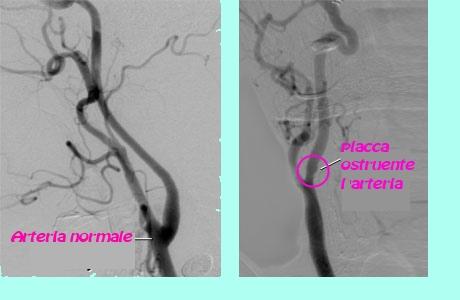

• la formazione di coaguli di sangue in una delle arterie molto piccole del cervello (trombosi). Questo è di solito preceduto da un restringimento graduale dei vasi sanguigni causato da un accumulo di grassi chiamato Aterosclerosi (ateromi = depositi di colesterolo e di tessuto adiposo sclerosi + restringimento) . il restringimento delle arterie del cervello è lo stesso il restringimento che si verifica nelle arterie del cuore che precedono un attacco di cuore.

• ecografia carotidea è un test per cercare restringimento dei vasi sanguigni nella parte anteriore del collo che forniscono il maggior apporto di sangue al cervello.